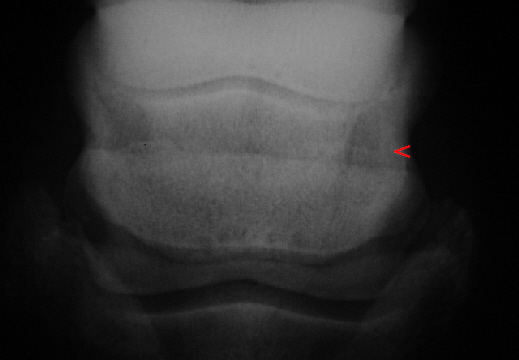

Beispiel für eine Zubildung am oberen Rand des Strahlbeines. Auch am unteren Rand finden sich schwächer ausgeprägte Zubildungen und die Gefäßkanäle sind diffus abgegrenzt. Dies sind Befunde im Bereich der Kategorie III bzw. Grad 3.